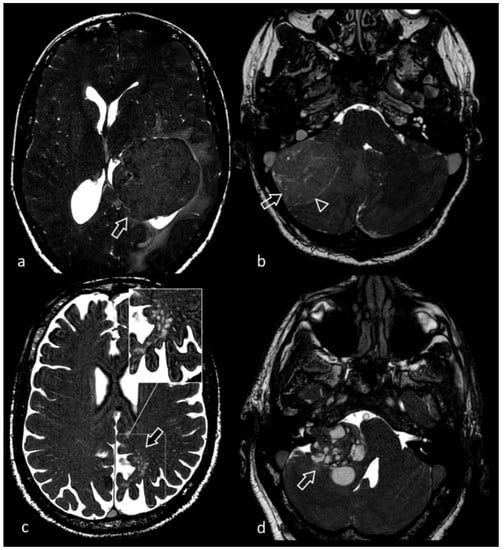

3.6. Neurocysticercosis

3.8. Cerebellopontine Angle Lesions